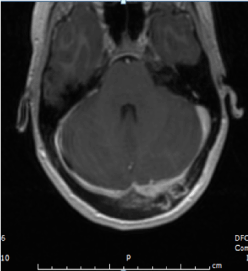

27-year-old female with past medical history significant for IVDU presented to emergency department with neck pain, and occipital headache for 1 week. She admitted to recent heroin use. Her vitals were significant for, blood pressure of 102/67 mm Hg, pulse of 116 beats per minute, temperature 36.9 °C (oral), respiratory rate of 19 breaths per minute, oxygen saturation of 96% on room air. Physical exam was remarkable for left shoulder hematoma and track marks bilaterally on arms. WBC count was with normal range. Blood cultures grew MRSA, susceptible to vancomycin. Transesophageal echocardiogram showed 6.9 mm tricuspid valve vegetation. MRI brain showed left subdural empyema (Figure 1) and associated osteomyelitis within the overlying occipital bone (Figure 2). MRI head showed left transverse sinus thrombosis extending superiorly into an occipital lobe cortical vein with evidence of collateralization of flow within the overlying occipital bone (Figure 3). Neurosurgery did not recommend any surgical intervention. Follow up head MRI showed decrease in the size of the subdural empyema. Patient completed 6-week course of vancomycin and her symptoms improved.

Figure 1. MRI brain showing left subdural empyema.

Figure 2. MRI brain showing osteomyelitis within the overlying occipital bone.